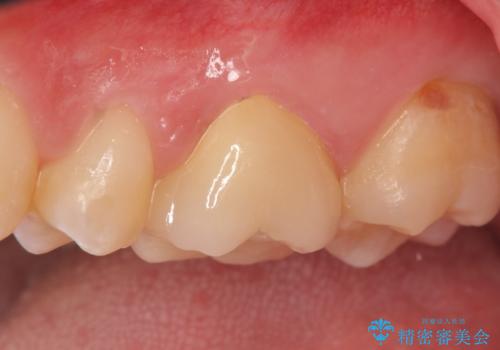

- 矯正治療前の虫歯治療で通われている患者様です。レントゲン上で神経に近い虫歯様の大きな影が認められ、虫歯を削ったところ神経には近かったものの歯質欠損量としてはインレーが適用となったため、セラミックインレーを被せることとなりました。

今回行った方法は歯髄保存療法のうちの間接覆髄法と治療で、虫歯の除去や窩洞形成などで残った歯質が薄く神経との距離が近い場合に、水酸化カルシウム製剤のような覆髄材で保護層を作り、外来刺激の遮断と二次的な象牙質の形成を促す